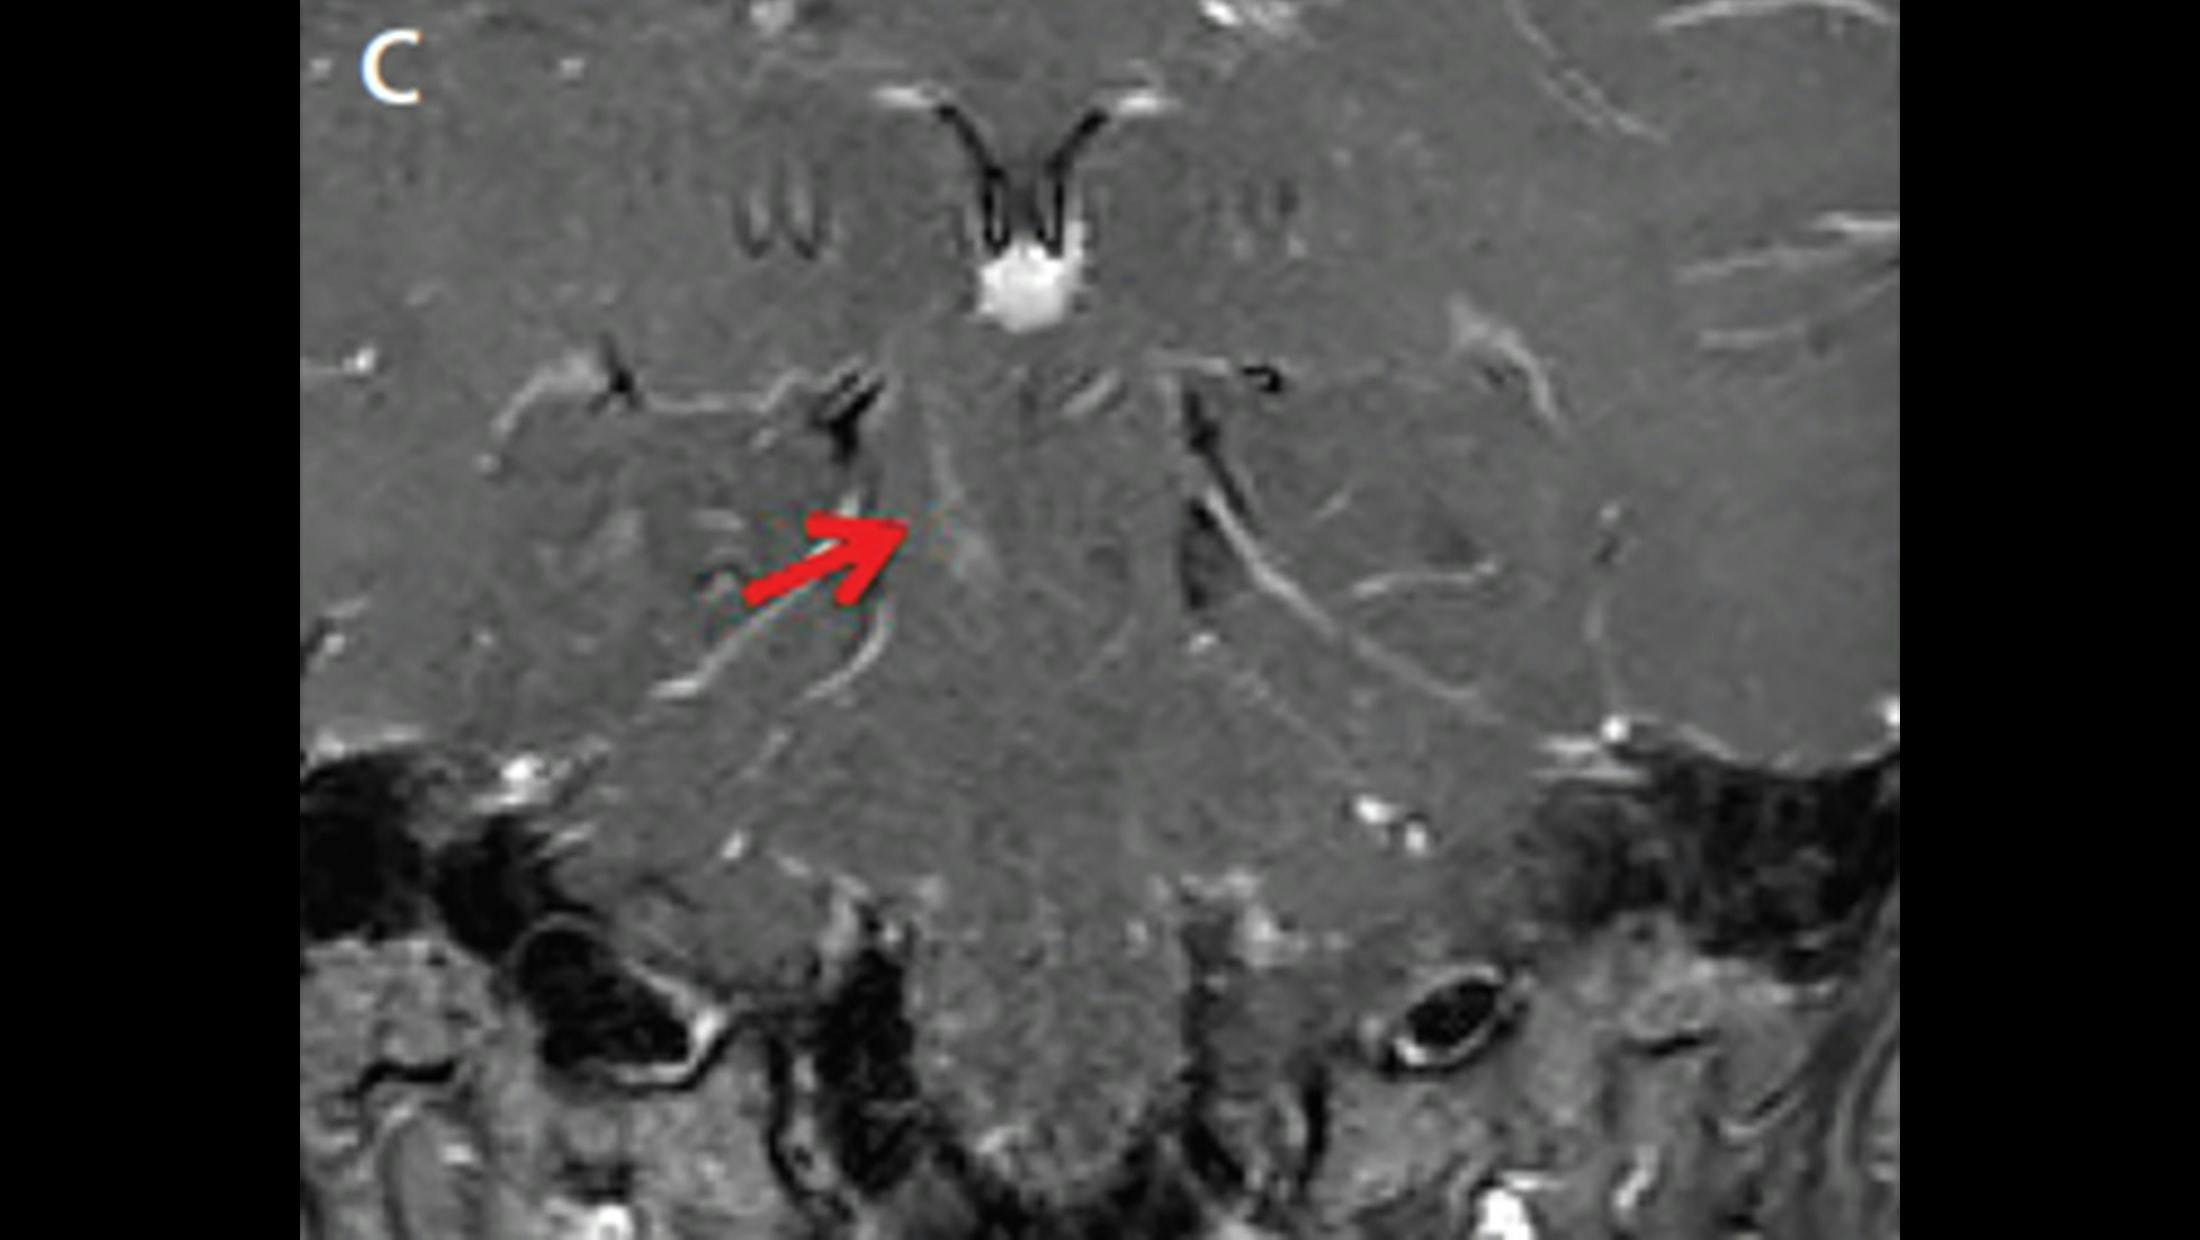

Coronal T1 postgadolinium MRI in a patient with AQP4+ NMOSD demonstrating an enhancing linear brainstem lesion in the right cerebral peduncle.